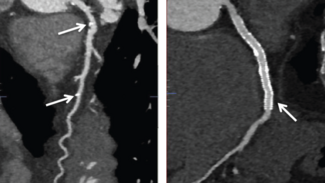

This image series shows the use of intravascular ultrasound and optical coherence tomography in the diagnosis and treatment of a 52-year-old male patient with hypertension admitted for inferior ST-segment-elevation myocardial infarction.